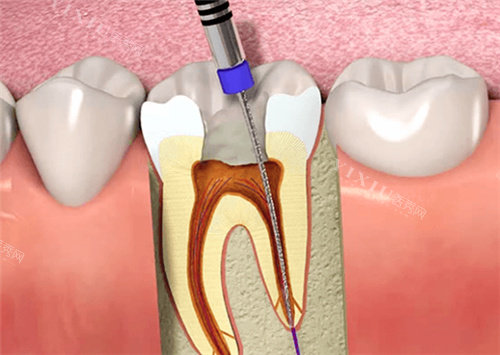

八、根管治疗价格

根管治疗是治疗牙髓病和根尖周病的有效方法,柳州东成口腔的根管治疗项目由经验充足的医生团队操作。

常规根管治疗:1360 元起

显微根管治疗:1300 元起

前牙根管治疗:700 元起

双尖牙根管治疗:1000 元起

磨牙根管治疗:1000 元起

牙齿咬合痛治疗:2262 元起